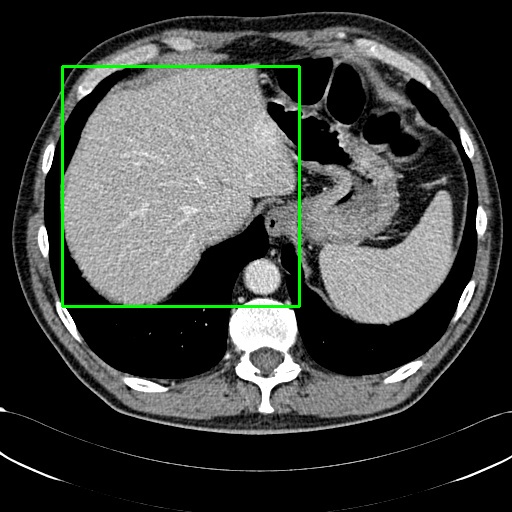

Refer to caption

(a) Example of locating ROI via SAT[29].

(b) Example of locating ROI via BA-Transformer [30].

(c) Example of locating ROI via Chexmask [31].

Figure 6: Example of ROIs and their corresponding textual descriptions.

We employ various strategies to locate Regions of Interest (ROIs) in images. For datasets that already include localization annotations, such as segmentation masks or bounding boxes, we derive the ROIs from these existing annotations. Specifically, bounding boxes are directly used as the ROIs, while segmentation masks are converted to ROIs by creating the smallest bounding box that covers the mask. When such localization annotations are not available, we apply different pretrained expert models listed in the Appendix to generate ROIs. For text-prompt driven grounding model[29], we use disease and organ information in coarse captions as text prompts to guide the model in segmenting specific parts. Examples of generated ROIs from various modalities with different models are demonstrated in Figure 6. It is important to note that for modalities such as X-ray and MRI scans viewed from the z-axis, our ROI localization employs a coordinate system relative to the human body, resulting in a left-right reversal in the image representation.

Without ROIs, the original description is limited to a brief global analysis of the image. However, with ROIs, MLLMs  can perform a more detailed local analysis of the ROIs and assess the impact of lesion ROIs on the surrounding normal regions, as demonstrated in Figure 4.